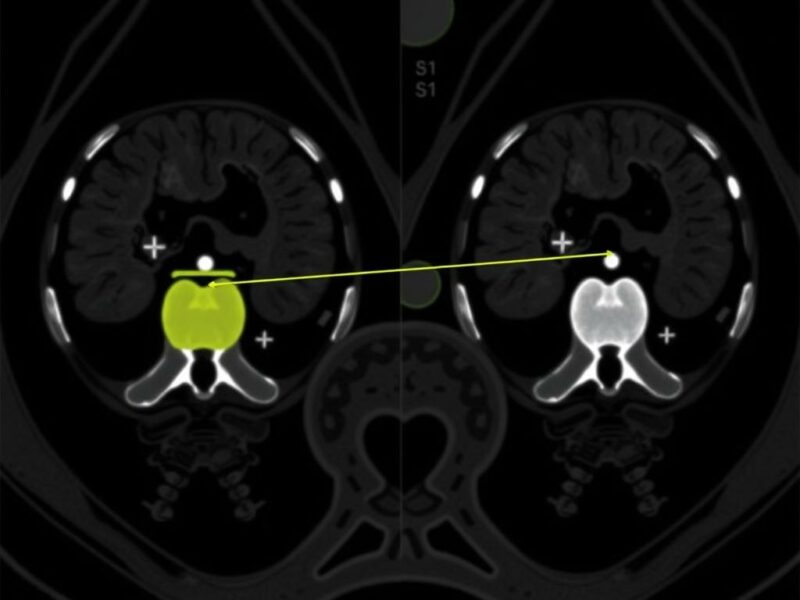

Un flujo típico de IA integrado en el proceso de lectura tomográfica puede incluir los siguientes pasos: preprocesado de la imagen (normalización, eliminación de artefactos), detección automática de la región abdominal relevante, segmentación del apéndice, cálculo de métricas (diámetro, grosor de pared, realce), evaluación de signos periapendiculares y, finalmente, una clasificación probabilística que sugiere la presencia o ausencia de apendicitis y su posible complicación. Este resultado se presenta al radiólogo dentro del visor de imágenes, enfatizando hallazgos y proponiendo métricas que el clínico puede revisar y aceptar o refutar.

La integración de IA en el diagnóstico por TC puede aportar varias ventajas prácticas que conviene destacar de forma clara y realista. Primero, la detección temprana y el triage: sistemas bien entrenados pueden identificar imágenes con alta probabilidad de apendicitis y marcarlas para lectura prioritaria, reduciendo el tiempo hasta la intervención en casos urgentes. Segundo, la estandarización: la IA puede reducir la variabilidad interobservador al ofrecer medidas cuantitativas uniformes (por ejemplo, diámetro apendicular exacto, densidad del tejido periapendicular), lo que facilita decisiones basadas en umbrales objetivos.

Integrar IA en el flujo de trabajo clínico no es solo instalar un software: implica adaptaciones técnicas, formación del personal, protocolos de validación y procesos de gobernanza. Un modelo idealmente se integra en el PACS o visor de trabajo para que el resultado aparezca como una capa adicional: zonas marcadas, medidas cuantitativas y una probabilidad de apendicitis. El radiólogo revisa el estudio con la ayuda del algoritmo, confirma o corrige las anotaciones y dicta un informe final que incorpora la información aportada por la IA.